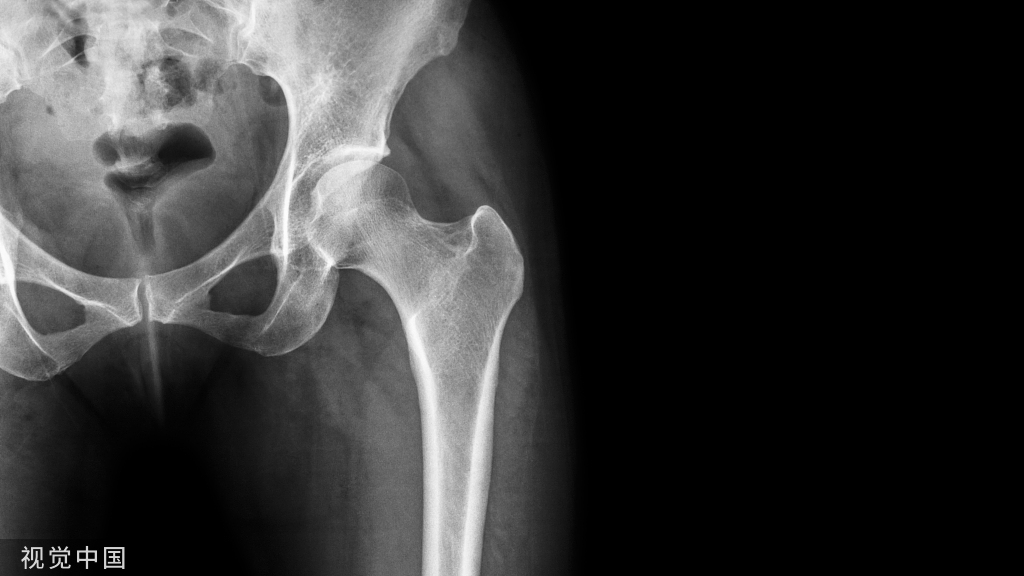

髋臼骨折由高能量损伤所致,多见于青壮年,骨折块移位可导致髋关节匹配丧失,若不经复位而任其畸形愈合,将导致股骨头与髋臼接触面减小,局部压力增加,引起关节软骨塌陷,最终导致创伤性关节炎。

髋臼骨折由高能量损伤所致,多见于青壮年,骨折块移位可导致髋关节匹配丧失,若不经复位而任其畸形愈合,将导致股骨头与髋臼接触面减小,局部压力增加,引起关节软骨塌陷,最终导致创伤性关节炎。髋臼骨折手术治疗需恢复髋臼形态、接触区几何形态和关节内压力分布

臼顶为支持股骨头的关节面负重区,髋臼骨折手术治疗目的均在于解剖修复臼顶及其下方的股骨头的同心圆复位。